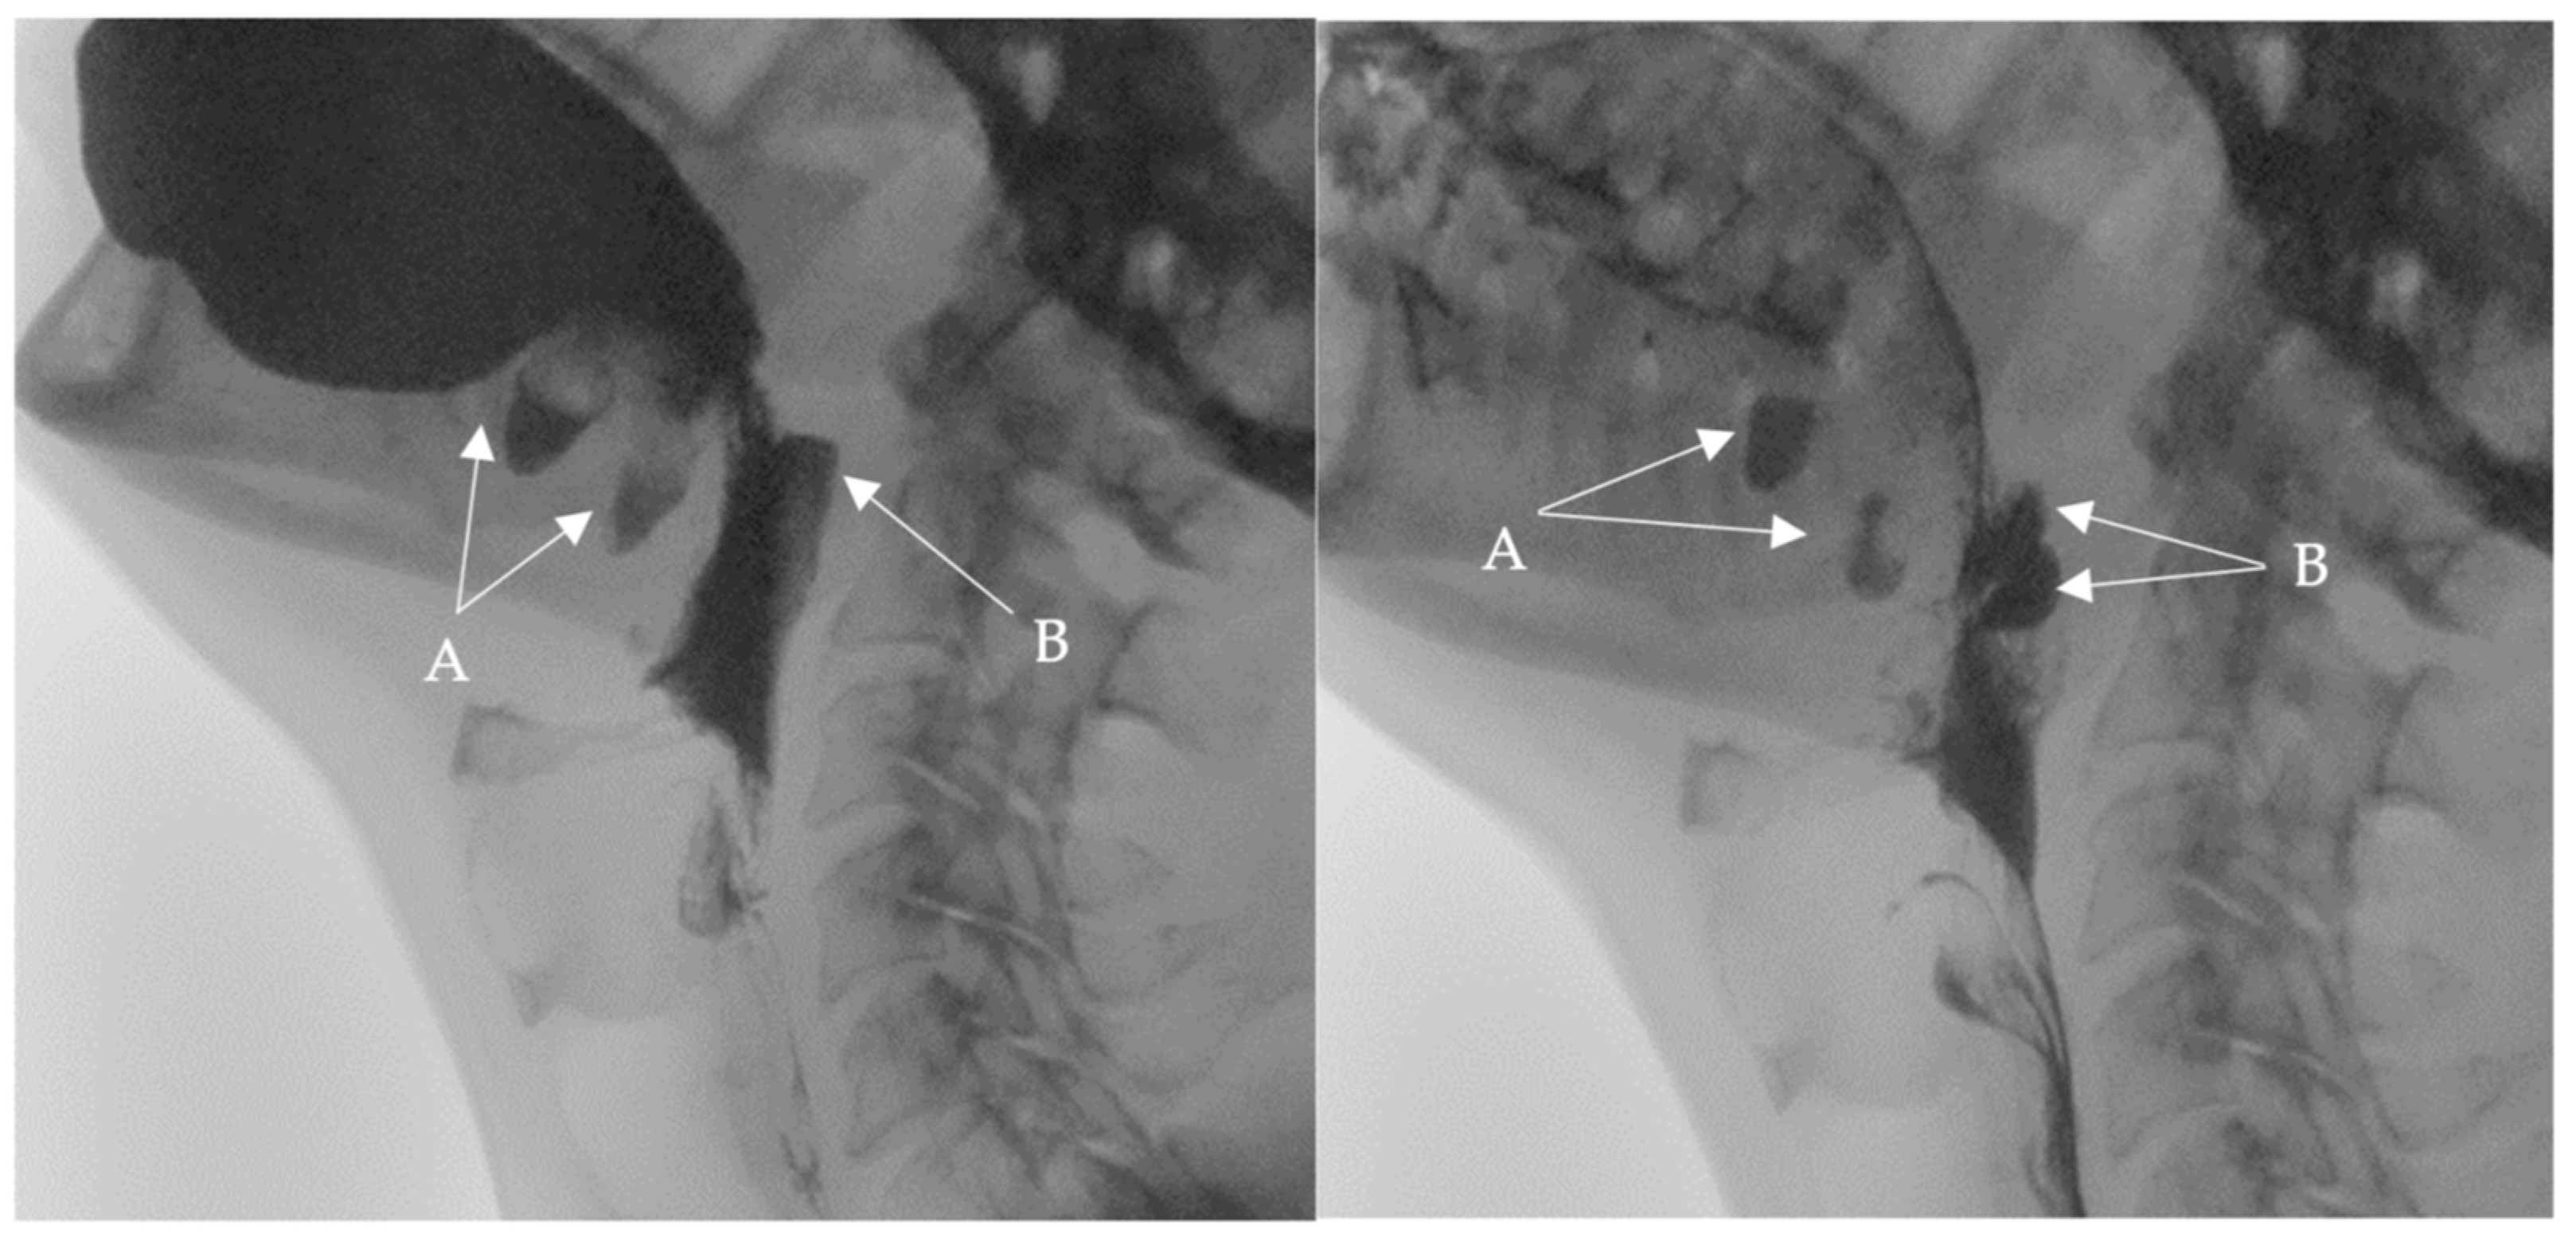

Following these findings, the ENT specialist reassessed the patient and confirmed the presence of bilateral diverticula in the buccal area and posterior pharyngeal walls, in alignment with the VFSS findings. The two diverticula were located on the right and left side inferiorly in the buccal area (Figure 3) and (Figure 4), and two were located on the right and left side superiorly in the oropharynx area. (Figure 5) and (Figure 6).

Figure 5. Selected still image captured during the FEES assessment: arrow heads pointing to the opening of a diverticulum located in the left superior aspect of the oropharynx area.

Medicina 60 01628 g005

Figure 6. Selected still image captured during the FEES assessment: arrow heads pointing to the opening of a diverticulum located in the right superior aspect of the oropharyngeal area.